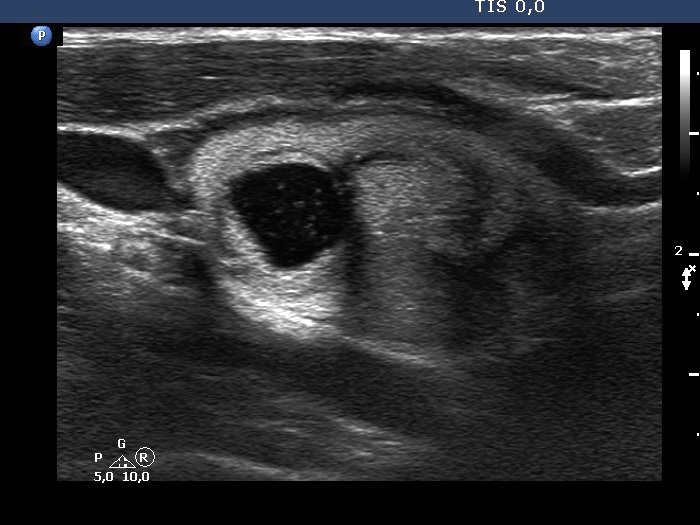

The composition of the nodule - case 636

Examination one year later (ultrasonographic picture 4)

Left lobe, another longitudinal scan.